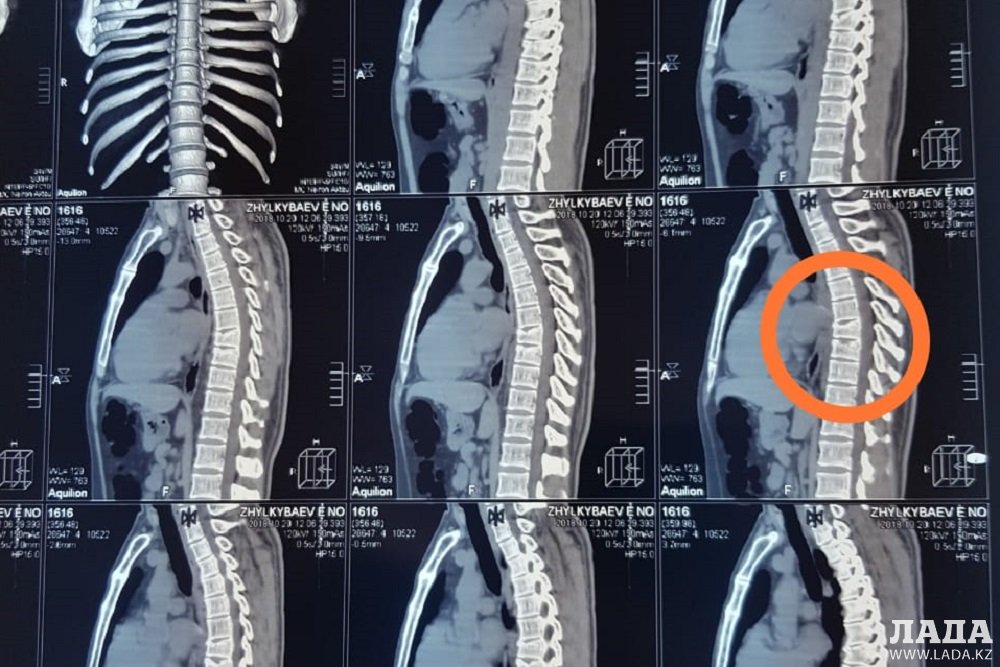

- Трасса не освещается. Верблюда увидел уже поздно. Решил уйти от столкновения с ним и вылетел на обочину. После того, как пришел в себя, вылез из машины. Две машины проехали мимо, хотя видели меня и мой автомобиль. Помогли ребята, которые ехали за мной. Меня отвезли в больницу поселка Шетпе. Там осмотрели и отправили в в областную больницу Актау. Врачи сказали, что ничего серьезного, и отправили домой. Уже на следующий день после обследования в частной клинике выявили травму трех позвонков, – рассказал Есен Джилкибаев.